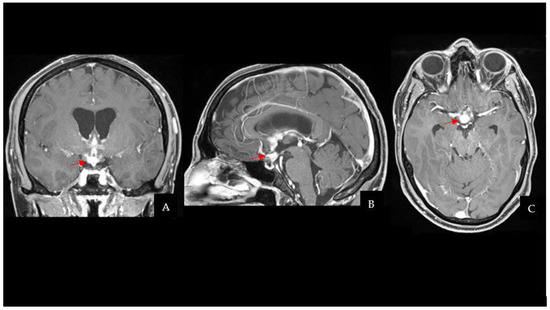

The CT scan was followed by a cerebral magnetic resonance imaging (MRI) scan that showed a pseudonodular suprasellar lesion, isointense with grey matter on both T1- and T2-weighted images, with heterogeneous enhancement after contrast administration. The lesion extended from the pituitary peduncle to the hypothalamic region and the optic tracts, with a maximum craniocaudal extension of 3 cm.

Taking into account the patient past medical history of testicular GCT, neuroradiological findings were considered compatible with a CNS GCT (Figure 1). However, pituitary adenoma, craniopharyngioma, metastases, sellar region lymphoma and meningioma had to be ruled out. Hence, a neurosurgical hospitalization for further diagnostic investigations was indicated.

Figure 1. CE-T1Weighted MRI scan showing a pseudonodular suprasellar lesion extended from the pituitary peduncle to the bilateral hypothalamic region, with a maximum craniocaudal extension of 3 cm (the lesion is highlighted by red arrows). (A) Coronal sequence. (B) Sagittal sequence. (C) Axial sequence. Abbreviations: contrast-enhanced T1Weighted (CE-T1W); magnetic resonance imaging (MRI).